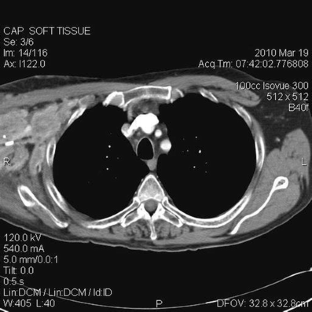

Sikaria, S., Heim-Hall, J., Diaz, E.H. et al. Partial response of a rare malignant metastatic diffuse tenosynovial giant cell tumor with benign histologic features, treated with SCH 717–454, an insulin growth factor receptor inhibitor, in combination with everolimus, an MTOR inhibitor. Targ Oncol 9, 73–79 (2014). https://doi.org/10.1007/s11523-013-0267-8